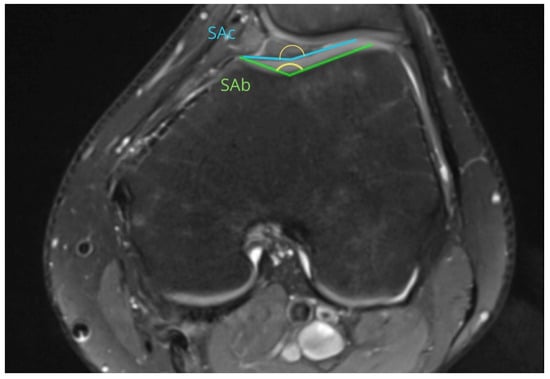

| SA | Sulcus angle |

| SAb | 148.26 ± 13.82 | 149.93 ± 10.66 | 0.64 |

| SAc | 156.06 ± 12.43 | 159.01 ± 10.69 | 0.37 |